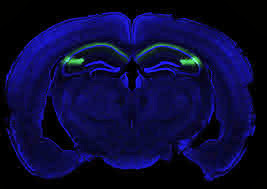

Researchers have found in mice that a formerly obscure region of the hippocampus called CA2 is important for social memory, the ability of an animal to recognize another of the same species. Identifying the role of this region could be useful in understanding and treating disorders characterized by altered social behaviors such as schizophrenia, bipolar disorder, and autism. Funded in part by the National Institute of Mental Health (NIMH), the study was published last month online in Nature.

To circumvent these problems, Siegelbaum, a neuroscience professor at Columbia University and a Howard Hughes Medical Institute Investigator, and Frederick L. Hitti, an M.D.-Ph.D. student, generated a special transgenic mouse in which the CA2 neurons could be selectively inhibited in adult animals. Once these neurons were inactivated, the mice underwent a series of behavioral tests.

Normally when a mouse encounters another mouse it does not know, it gives it a “sniff test” and is more interested in this new mouse versus a familiar acquaintance. The CA2-inactive mouse, however, shows no recognition of mice it has seen before and ends up sniffing indiscriminately familiar and novel mice. The mice showed no loss in the ability to discriminate social or non-social odors, such as food buried deeply in its litterbox. Although a pronounced loss of social memory is seen in the CA2-inactive mice, the mice did not experience changes in other hippocampal-specific behaviors such as spatial and contextual memory, and could still distinguish between novel and familiar inanimate objects.

"However, the role of CA2, a relatively small region of the hippocampus sandwiched between CA3 and CA1, has remained largely unknown," said senior author Steven A. Siegelbaum, PhD, professor of neuroscience and pharmacology, chair of the Department of Neuroscience, a member of the Mortimer B. Zuckerman Mind Brain Behavior Institute and Kavli Institute for Brain Science, and a Howard Hughes Medical Institute Investigator. A few studies have suggested that CA2 might be involved in social memory, as this region has a high level of expression of a receptor for vasopressin, a hormone linked to sexual motivation, bonding, and other social behaviors.

To learn more about this part of the hippocampus, the researchers created a transgenic mouse in which CA2 neurons could be selectively inhibited in adult animals. Once the neurons were inhibited, the mice were given a series of behavioral tests. "The mice looked quite normal until we looked at social memory," said first author Frederick L. Hitti, an MD-PhD student in Dr. Siegelbaum's laboratory, who developed the transgenic mouse. "Normally, mice are naturally curious about a mouse they've never met; they spend more time investigating an unfamiliar mouse than a familiar one. In our experiment, however, mice with an inactivated CA2 region showed no preference for a novel mouse versus a previously encountered mouse, indicating a lack of social memory."